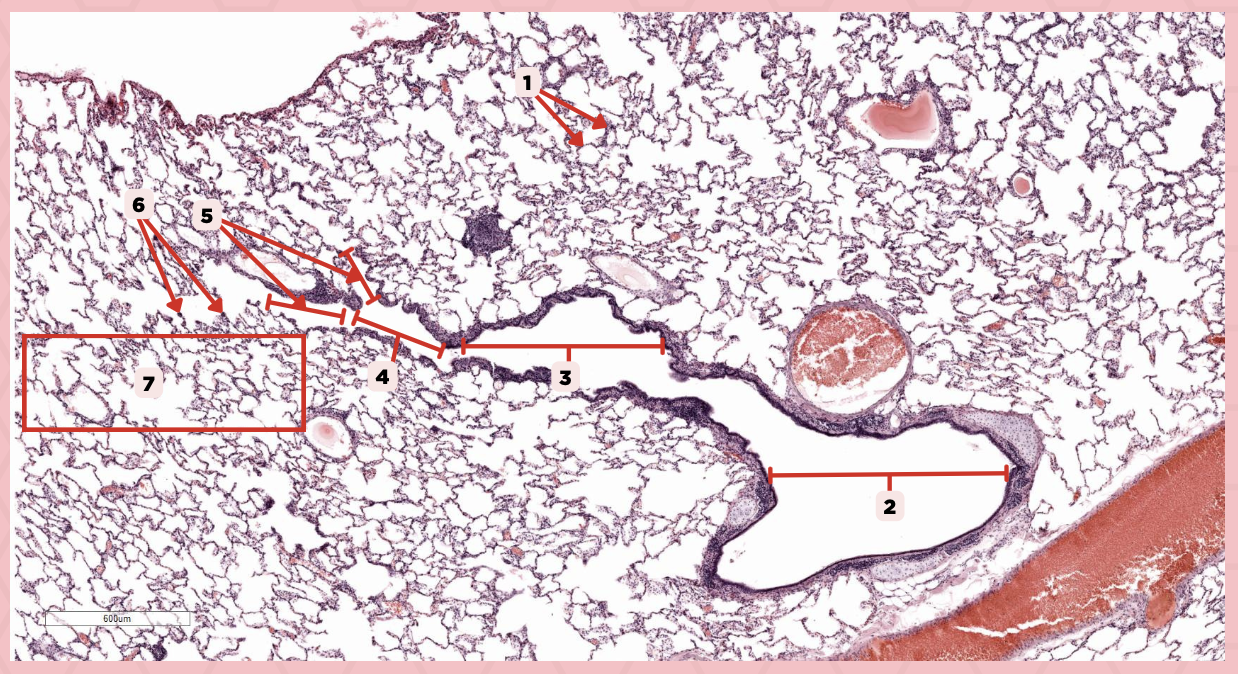

Lumens and Interalveolar septa

Name the irregular spaces and the fine threads of tissue that separate them.

Visceral pleura

Identify the structure labeled as 1.

Alveoli

Identify the structure labeled as 2.

Bigger and smaller intrapulmonary bronchi

What are the two types of intrapulmonary bronchi?

Pseudostratified epithelium (bigger bronchioles), Simple columnar or cuboidal (smaller)

What are the types of epithelium in No. 3?

Interalveolar septa

Identify the structure labeled as 1.

Intrapulmonary bronchi

Identify the structure labeled as 2.

Bronchiole

Identify the structure labeled as 3.

Terminal bronchiole

Identify the structure labeled as 4.

Respiratory bronchiole

Identify the structure labeled as 5.

Alveolar ducts

Identify the structure labeled as 6.

Alveolar sacs

Identify the structure labeled as 7.